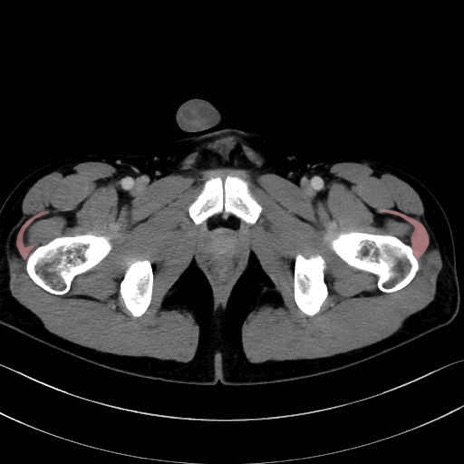

中殿筋 (Gluteus medius)